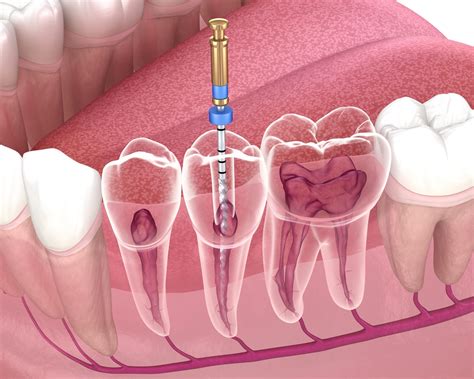

Endodontics stems from the Greek words "endo" (inside) and "odont" (tooth). Therefore, the literal definition is "inside the tooth." The primary goal of an endodontic specialist is to manage the health of the pulp, which contains nerves, blood vessels, and connective tissue. When this tissue becomes inflamed or infected—often due to deep decay, repeated dental procedures, or a traumatic injury—it causes significant pain and threatens the integrity of the tooth.

By specializing in the interior health of the tooth, these professionals utilize advanced technology, such as surgical microscopes and digital imaging, to perform intricate procedures. This high level of precision allows them to navigate the tiny, complex canals within the tooth roots to remove bacteria and restore function.

• Root Canal Therapy: The standard procedure for removing infected pulp, cleaning the canal system, and sealing the tooth to prevent future infection.

The actual root canal or surgery involves isolating the tooth, cleaning the canals, and filling them with a biocompatible material called gutta-percha. After the procedure, the tooth is usually capped with a crown or filling to restore it to its full functionality. Most patients find that they can return to their normal daily activities almost immediately.